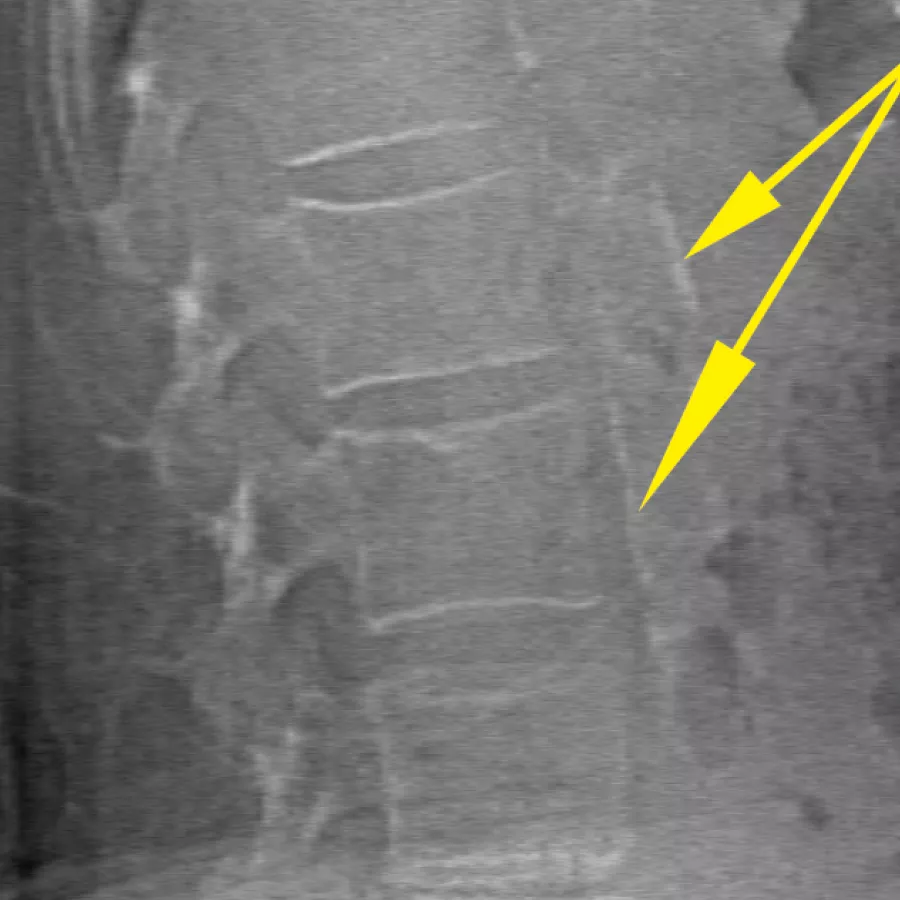

O Horizon DXA gera imagens de qualidade radiográfica de todo o fémur para a avaliação de potenciais fraturas atípicas do fémur.31 Uma radiografia rápida de 15 segundos revela um espessamento cortical do osso, fazendo com que seja fácil e rápido monitorizar os efeitos da terapia com bisfosfonatos ao longo do tempo.

Veja a placa calcificada na aorta abdominal, que pode ser um forte indicador de doenças do coração e AVC, duas das principais causas de morte em homens e mulheres.

Avalie o risco de fratura através da combinação de uma medição precisa da densidade óssea com imagens vertebrais de alta resolução. É possível identificar fraturas da coluna vertebral com uma imagem de baixa dose e energia única em 10 segundos.

Melhore a precisão e reduza os erros de análise pós-exame com a colocação precisa e assistida por software de espaços entre os discos vertebrais para análise gráfica.